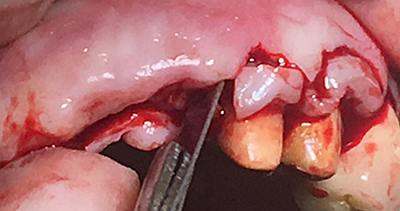

設(shè)計(jì):1.僅做牙槽嵴頂水平切口,不做垂直切口,2.缺牙區(qū)由三顆牙改成兩顆牙,3.鄰牙冠延長(zhǎng)。

水平切口,鄰牙冠延長(zhǎng)。

擴(kuò)孔,檢查方向。

大家注意這個(gè)動(dòng)作,雖然不翻瓣,但要將唇側(cè)倒凹處骨膜剝離。